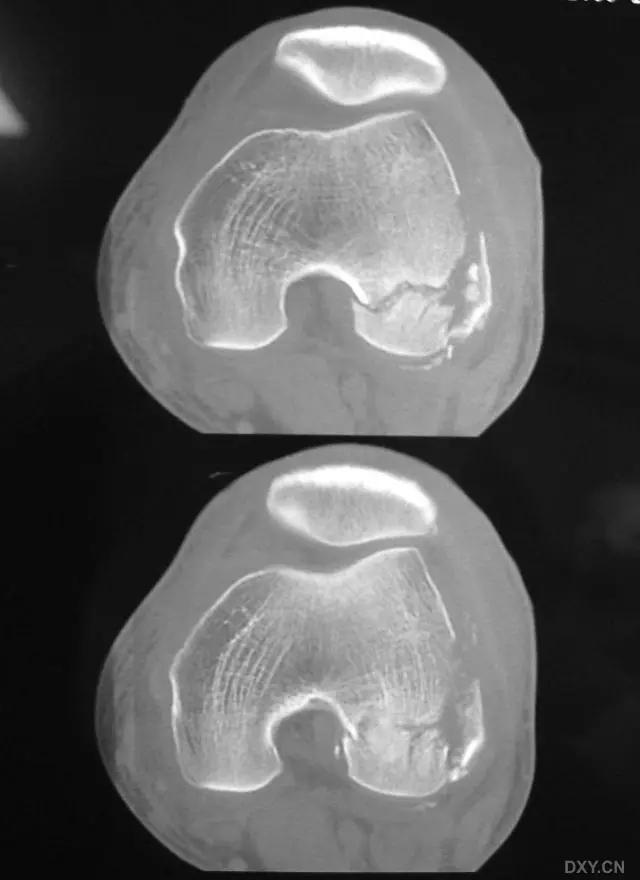

6. Jefferson 骨折

寰椎环的压缩性骨折,骨折是由枢椎压缩性外力引起,骨折多发生在寰椎前侧后侧以及侧方小关节。

第一颈椎双侧性前、后弓骨折,X 线片上很难发现骨折线,有时在正位片上看到 C1 关节突双侧性向外移位,侧位片上看到寰椎前后径增宽及椎前软组织肿胀阴影,CT 检查最为清楚,而 MRI 检查智能显示脊髓损伤情况。

A 图是稳定的 Jefferson 骨折(横韧带完整)轴位像。B 图是不稳定的 Jefferson 骨折(横韧带撕裂)轴位像